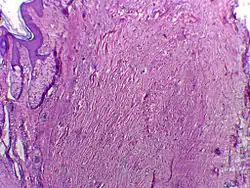

Une chéloïde, ou cicatrice chéloïdienne, est une forme de cicatrice résultant d’une excroissance du derme au niveau d’une blessure guérie. Elle se présente sous forme de lésions fermes, caoutchouteuses ou des nodules brillants, fibreux et sa couleur varie du rose au chair (pour les peaux claires) ou du rouge au brun foncé (pour les peaux foncées). Une cicatrice chéloïde est bénigne, non contagieuse et généralement accompagnée de fortes démangeaisons, voire de douleurs vives ; sa texture évolue dans le temps. Dans les cas les plus graves, elle peut affecter le mouvement de la peau.